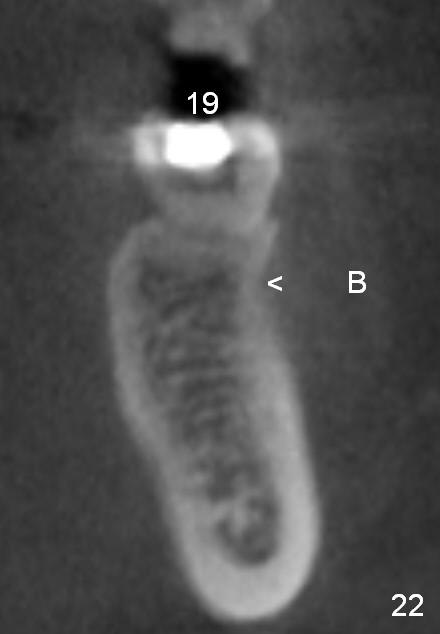

CBCT taken 15 months post cementation shows that the implant is buccally placed (Fig.21 B), associated with possible postop buccal plate resorption (as compared to Fig.23 (coronal section of the site of #19). The buccal plate is not only thinner than the lingual one, but also concave (Fig.22 <). The tooth center (i.e., septum; Fig.23 T) is more buccally located than the center of the basal bone (B). Considering the denser bone lingually, the initial osteotomy should be more lingually (^). If the implant develops infection, it will be replaced by a more lingually placed implant (Fig.24 green).